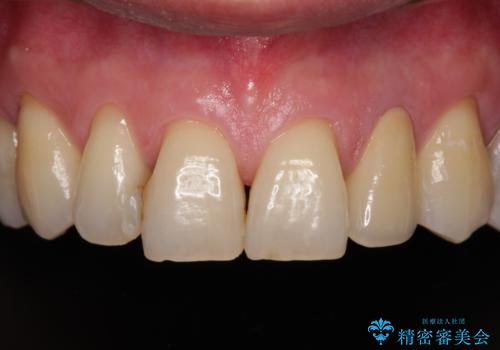

根管治療の土台のまま放置してしまった前歯 オールセラミッククラウンによる補綴治療

- 前歯の根管治療の際に、一時的に見た目を回復したままの状態で放置してしまったとのことで来院された患者様です。

土台の状態は良好であったため、仮歯に置き換えた上でオールセラミッククラウンにて補綴治療を行うこととしました。

見た目の改善はもちろんですが、ものが挟まらなくなったり、舌触りが良くなったりと、口腔内の状態が改善されました。